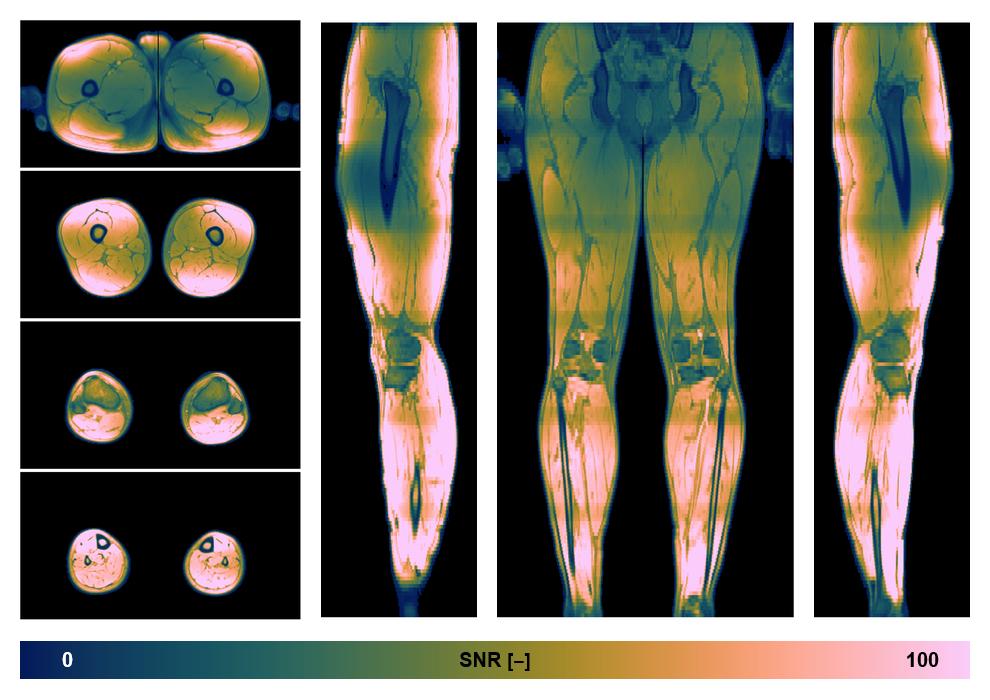

• SNR of the unweighted image

SNR distribution of the unweighted diffusion data.